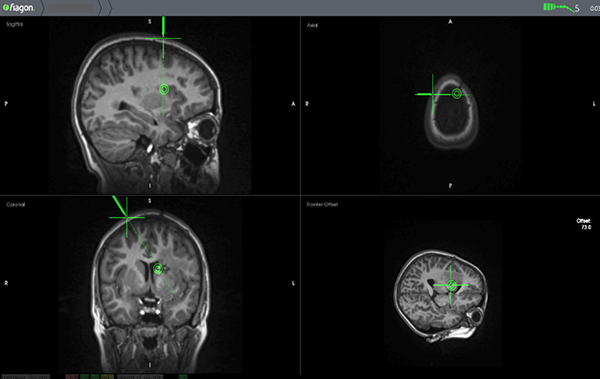

Para el presente caso se incorporaron las imágenes de RMI al equipo de neuronavegación electromagnético provisto de una cánula de aspiración maleable de 3 mm con cursor de navegación “on tip” incorporado (Faigon © origen Alemania). Se trazó la trayectoria marcando como blanco el sitio de aparente irrupción de la sangre en la pared lateral de la prolongación frontal durante el episodio hemorrágico de presentación del Cavernoma (Figura 3).

Figura 3: Planificación de la trayectoria mediante Neuronavegación.